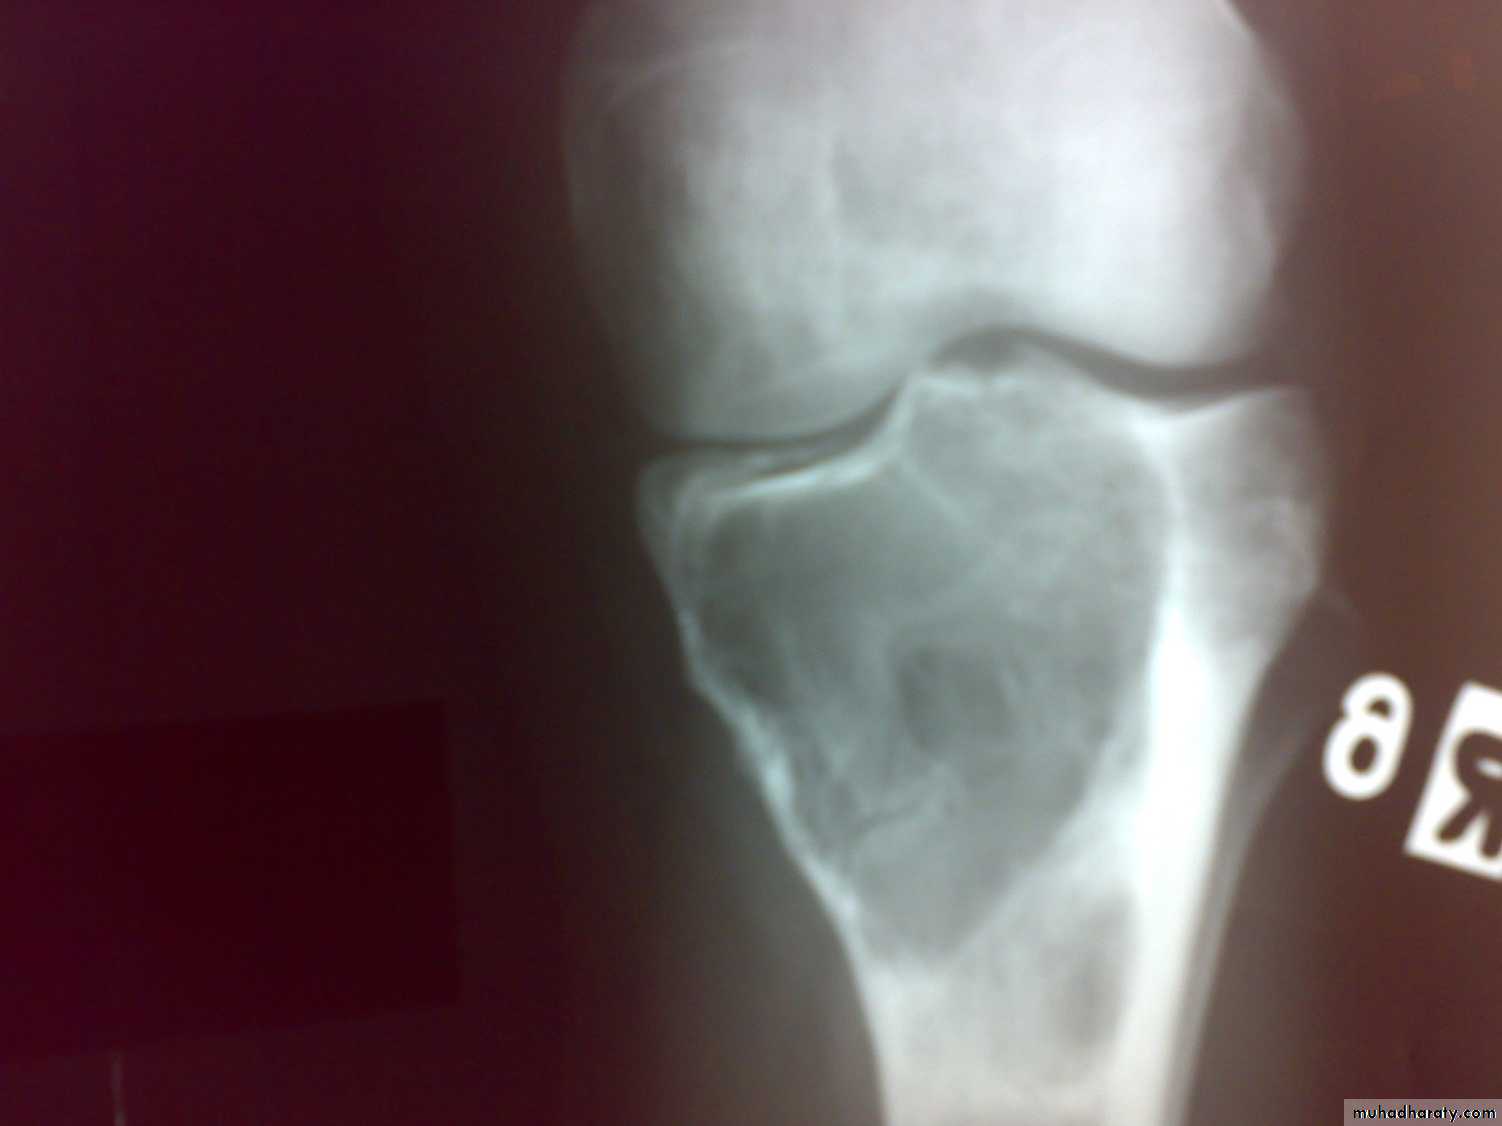

X-RAY:

show ill-define osteolytic lesion with overlying periosteal reaction in form of layers (onion peel). Radioisotope scanning show active area.